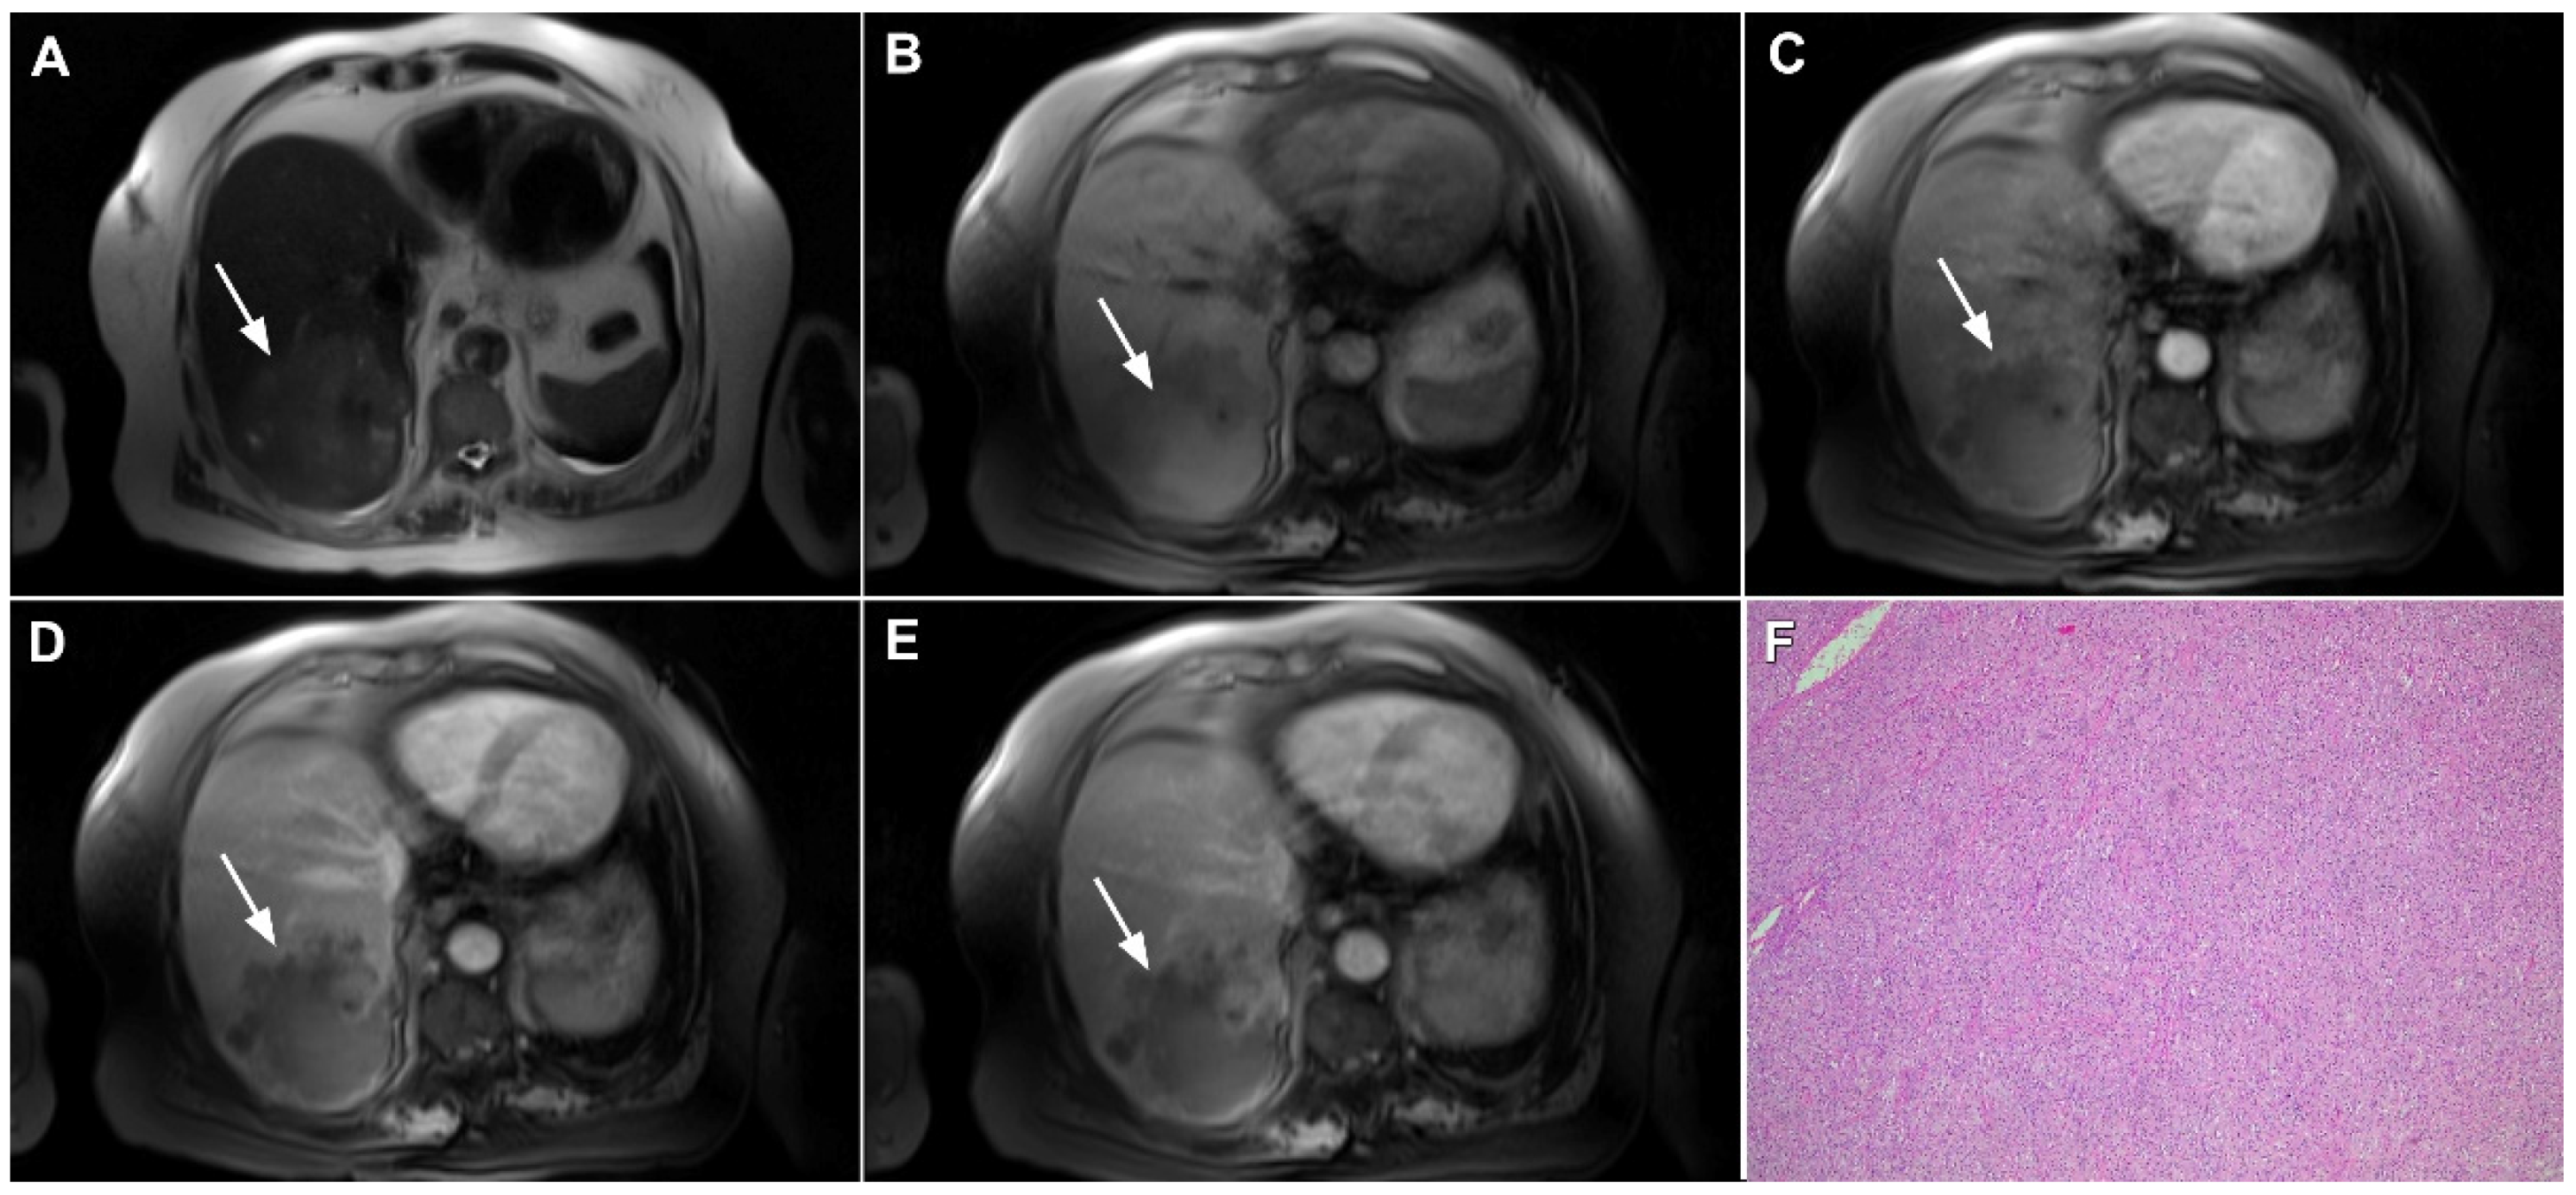

Figure 2.

Mass-forming intrahepatic cholangiocarcinoma in 72-year-old man. Irregular heterogeneously hyperintense lesion (arrow) on T2-weighted image (A) located in liver segments IVB and III with peripheral biliary dilatation is shown. On a plain T1-weighted image (B) the lesion (arrow) is hypointense with only discrete ring enhancement in the arterial phase (C) but without detectable enhancements in the portal venous (D) and delayed phases (E). Hematoxylin and eosin (H&E) staining (F) showed poorly differentiated cholangiocarcinoma (dashed arrow); normal liver parenchyma is also shown (arrow); original magnification ×40.